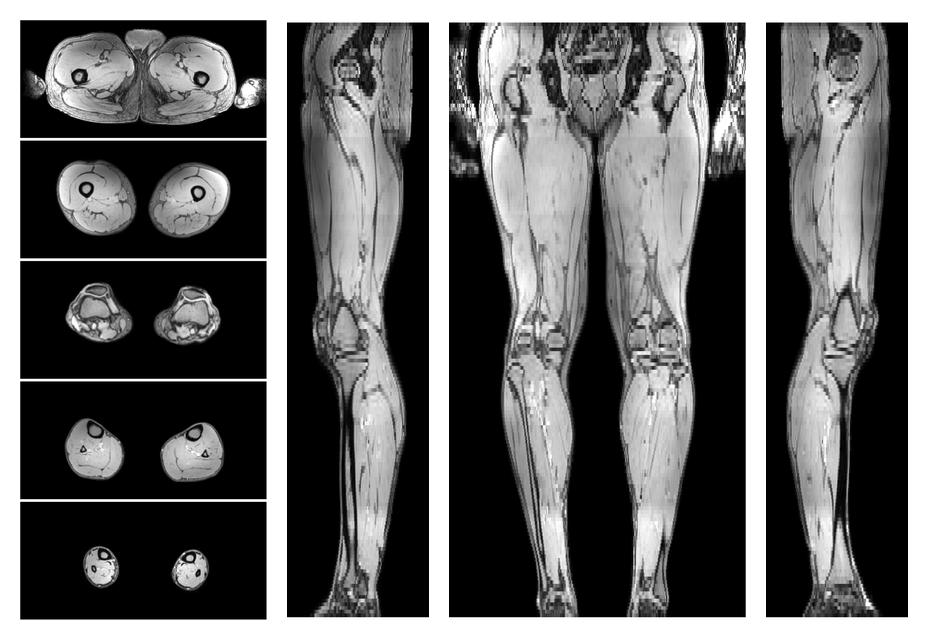

• Automated muscle and bone segmentation.

Overlay of automated muscle segmentation labels on dixon water image.